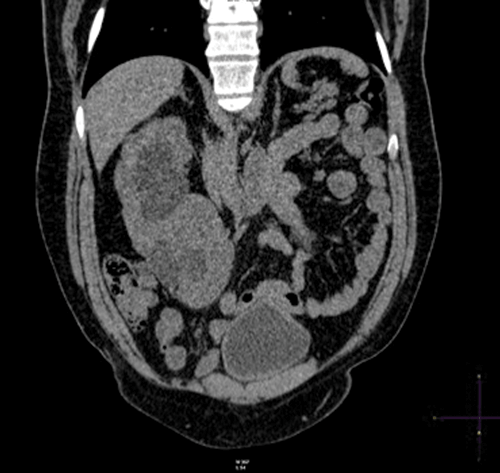

Case 2

Plain coronal CT kidney, ureter, bladder (KUB) demonstrating crossed fusion renal ectopia; one case in 1000.

Theories include: a. abnormally situated umbilical artery preventing normal cephalic migration. b. the ureteric bud crosses to the opposite side inducing nephron formation in the contralateral metanephric blastema.

Left to right ectopy is more common (3:1).